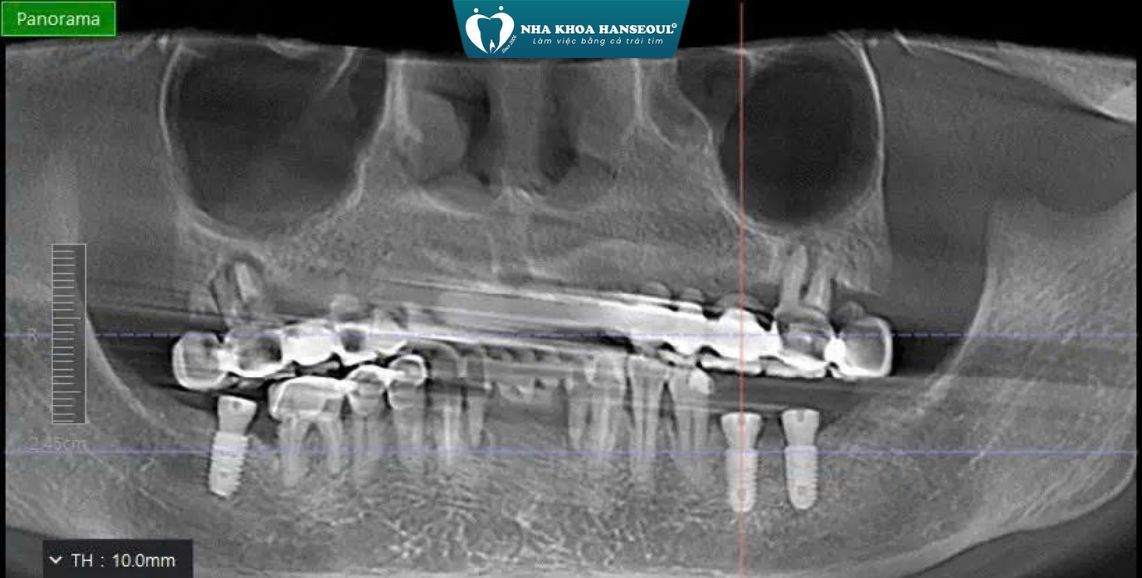

2 Giải pháp điều trị

Sau khi phân tích cấu trúc xương và sức khỏe tổng quát, bác sĩ đã xây dựng phác đồ điều trị cá nhân hóa, đảm bảo an toàn và hiệu quả lâu dài:

Cấy ghép 3 trụ Implant tại các vị trí: R36, R37, R47

Ghép xương kết hợp màng sinh học:

- Bổ sung thể tích xương bị tiêu

- Tạo nền xương vững chắc giúp Implant tích hợp ổn định

- Hạn chế nguy cơ tiêu xương về sau

Theo dõi tích hợp xương & gắn phục hình hoàn tất:

- Implant tích hợp tốt

- Phục hình hoàn chỉnh, khôi phục khả năng ăn nhai gần như răng thật